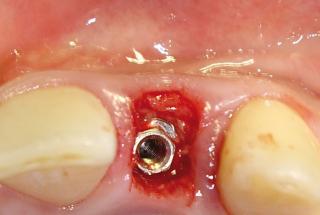

Clinical cases

MPI closely monitors clinical cases in the market to ensure their correct functioning and successful outcome.